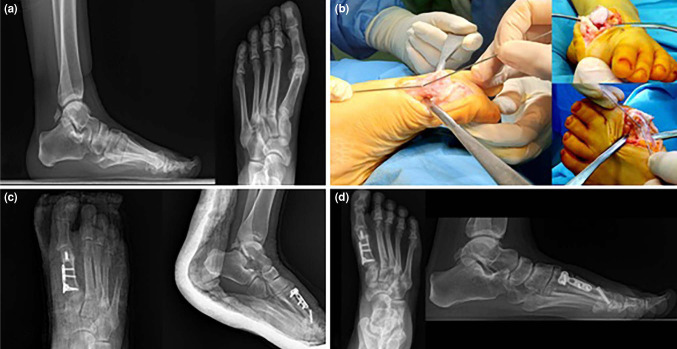

Double osteotomy in recurrence cases with distal metatarsal articular angle increase after hallux valgus distal surgery.

Objectives: The aim of this study was to evaluate the clinical and radiological results of the combined use of distal closed wedge and proximal open wedge osteotomies in cases of recurrent hallux valgus (HV) with an increased distal metatarsal articular angle (DMAA).

Patients and methods: Between January 2019 and December 2022, a total of 10 female patients (mean age: 48.8±10.8 years; range, 28 to 63 years) who underwent surgical treatment for recurrent HV with an increased DMAA were retrospectively analyzed. Pre- and postoperative anterior-posterior and lateral radiographs of the patients were taken. The intermetatarsal angle (IMA), DMAA, and HV angle (HVA) were measured and compared before and after surgery. The clinical outcomes of the patients were evaluated using the American Orthopaedic Foot & Ankle Society (AOFAS) score, Manchester-Oxford Foot Questionnaire (MOXFQ) score, and Maryland Foot Score (MARYLAND).

Results: The median follow-up was 33.1 (range, 24 to 78) months. Seven (70%) of the patients underwent surgery on the right side and three (30%) of the patients underwent surgery on the left side. The median time to recovery of osteotomies was 8 (range, 6 to 10) weeks. There was no loss of correction at minimal two years of follow-up. None of the patients developed postoperative infections. The postoperative HVA, IMA, DMAA values of the patients were statistically significantly lower than the preoperative values (p<0.05). The AOFAS and MARYLAND scores of the patients at six and 24 months after surgery were statistically significantly higher compared to the baseline (p<0.05). Considering the MOXFQ scores, the scores at six months and 24 months after surgery were statistically significantly lower than the scores before surgery (p=0.005 for both). Similarly, MOXFQ scores at 24 months after surgery were statistically significantly lower than those at six months (p=0.013), indicating that the clinical improvement obtained at six months continued to increase until 24 months.

Conclusion: The combination of distal closed wedge and proximal open wedge osteotomies for HV recurrence seems to be an effective surgical technique for correction of the deformity. Plate and screw fixation can increase the rate of bone union and accelerate postoperative mobilization of the patients. Further large-scale, long-term studies are needed to provide more comprehensive findings on the effectiveness of HV surgery and elucidate the effects of postoperative rehabilitation processes on recovery in order to optimize the treatment protocols.